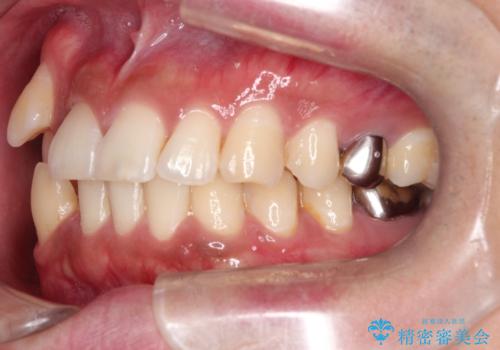

【ワイヤー矯正】八重歯と下の歯の凸凹を治したい

- 主訴:右上の八重歯と、下の歯の凸凹を治したい

上顎右側第一小臼歯と下顎右側第一小臼歯を抜歯しワイヤー矯正を行いました。

右側2級、左側1関係だったため、右側上下第一小臼歯を抜歯し、ワイヤー矯正を行いました。